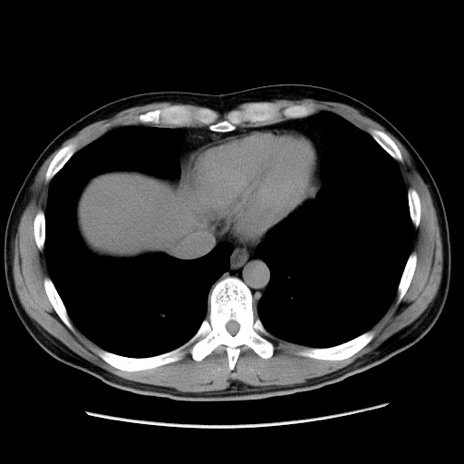

症例36(横断像)

【症例】20歳代 男性

【主訴】心窩部痛

【現病歴】今朝より上腹部痛あり。一旦軽快していたが再度出現したため救急要請。昨日夕に白身の魚を含む刺身を食べた。

【身体所見】BP 136/89mmHg、HR 74/min、BT 37.0℃、腹部:膨満、軟、心窩部に圧痛あり。反跳痛なし、筋性防御なし、腸雑音やや亢進あり。

【データ】WBC 17700、CRP 0.48